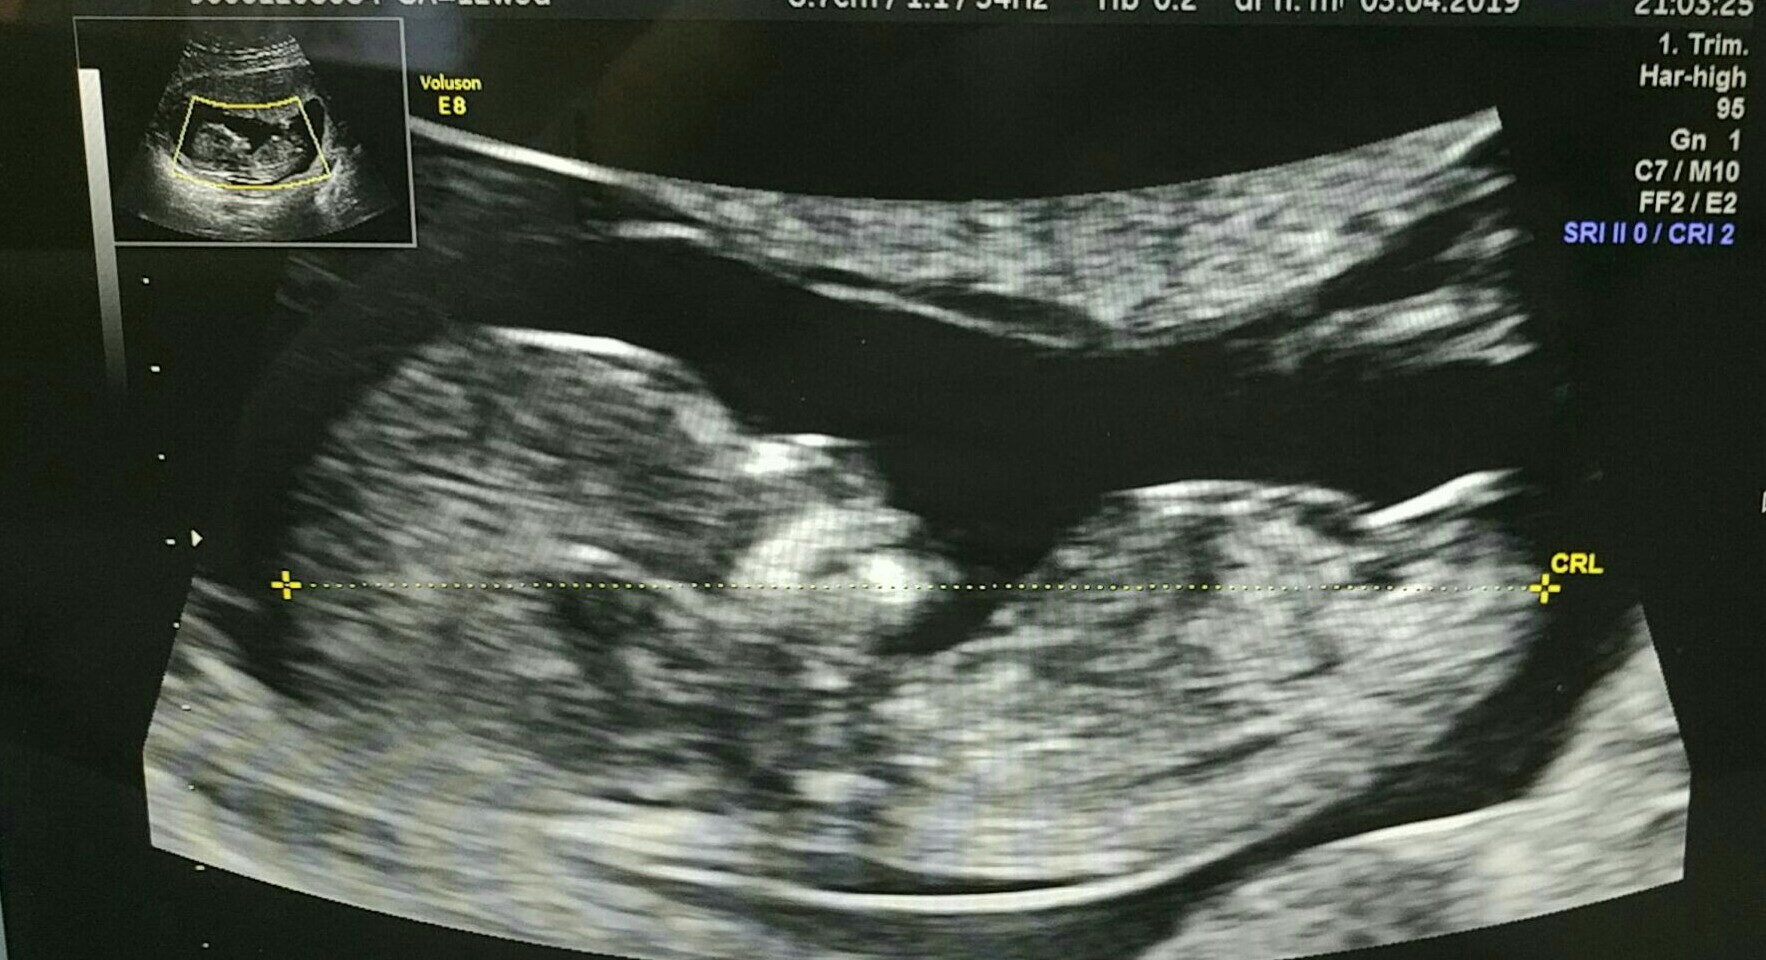

poprzednie usg wskazywało według tego samego lekarza na dziewczynkę a teraz te zdjęcia powyżej są świeże i mówi ten sam ginekolog że chłopiec

A lekarz mówił to z pewnością czy to tylko jego sugestia? Nie chce dyskutować z jego zdaniem, ale jak dla mnie to jest dziewczynka:))

Na tym z widocznym wyrostkiem mówił, że 99,99% książkowa dziewczynka. I mówi przyjdz za 2 tygodnie bedziesz miala prezent przedswiateczny. Przychodze i słysze, że raczej chłopak. Mówie do niego, że moze to sa opuchniete wargi sromowe czy cos, a on mowi, ze to nie jest czas aby wargi mogly byc opuchniete i na dziewczynke nie powinno byc widac po prostu nic, a tutaj odstaje :O

Właśnie gdyby mi nie powiedział nic byłoby lepiej, a tak to ja chciałam bardzo chłopca, 2 tygodnie temu stwierdzil ze moge zapomniec o chlopcu bo ksiazkowa dziewczynka i faktycznie na usg tym z wyrostkiem wyglada na dziewczynke, a teraz te najswiezsze usg mowi ze " raczej chlopiec" - dodam ze to lekarz ktory rzekomo sie nigdy nie myli, a u mnie juz sie pomylil w takim razie.

Może to fragment pępowiny tak się pokazał?